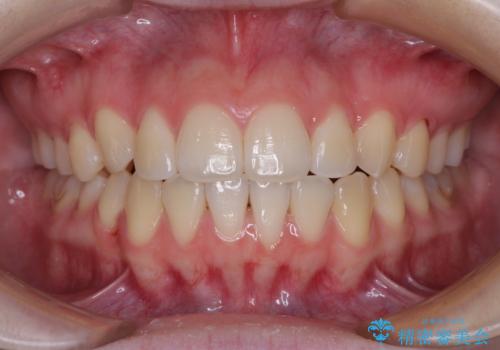

前歯のクロスバイトをインビザライン矯正で改善

- 前歯のデコボコと上下のクロスバイトを気にして来院された患者様です。

インビザラインを用い、IPR(歯と歯の間を削る)と歯列全体を拡大させることで、歯並びを整えていくこととしました。

上の前歯が下の前歯を乗り越える際、奥歯がほとんど咬めない時期があり、乗り越えた後も、インビザライン特有の奥歯の咬みにくさが続きました。

咬み合わせ改善のために治療期間を要しましたが、最終的に奥歯はしっかりと咬めるようになりました。